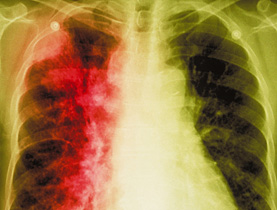

«El tabaquismo se mantiene como la causa principal para los tumores. Se considera que es la causa en uno de cuatro casos», asevera Cavalli. El médico recuerda además que el tabaquismo reviste un papel de primer orden en «una serie de enfermedades, principalmente de tipo cardiaco y respiratorio».

El presidente de la UICC menciona el ejemplo de China, donde se ha calculado que, si sigue esa tendencia, «en 2020 habrá 3 millones de personas que morirán cada año de cáncer de pulmón, sin pensar en los infartos e insuficiencias respiratorias».